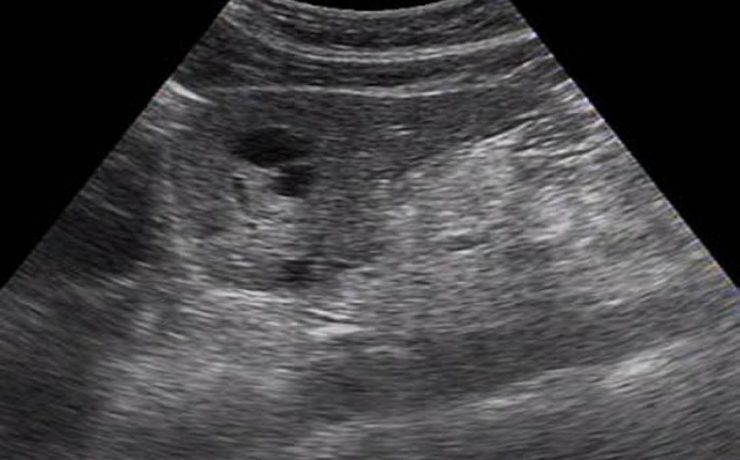

SEGMENTACIÓN HEPÁTICA. EVALUACIÓN ECOGRÁFICA

El hígado se encuentra en el hipocondrio derecho, pesa 1.5 a 2 kg en el adulto y se encuentra mantenido en su posición por la vena cava inferior, las venas suprahepaticas, el ligamento redondo del hígado y los ligamentos coronales y triangulares. Viendo al hígado de manera anterosuperior, se divide